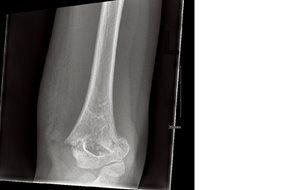

She was tearful, and used her right hand to hold her left elbow at a 45-degree angle for comfort and support. There was no tenderness over her left shoulder or wrist, and no abrasions or lacerations elsewhere on her body. Plain film radiographs of her left elbow were ordered (Fig. 1, a & b).

2. Acute, mildly displaced Type III supracondylar fracture with dorsal angulation of the distal humerus and associated joint effusion. (See below for further discussion of fracture types.)

These fractures are classified according to the Gartland classification system: type I, type II, and type III. In the simplest terms, type I is non-displaced, type II is displaced with an intact posterior periosteum and cortical continuity, and type III is displaced with disrupted anterior and posterior periosteum and lack of cortical continuity.2 This fracture is a type III because the AP projection shows lateral displacement. This could only occur if both the anterior and posterior cortices are broken.

Fig. 1a: Lateral view of left elbow.

Fig. 1b: AP view of elbow.